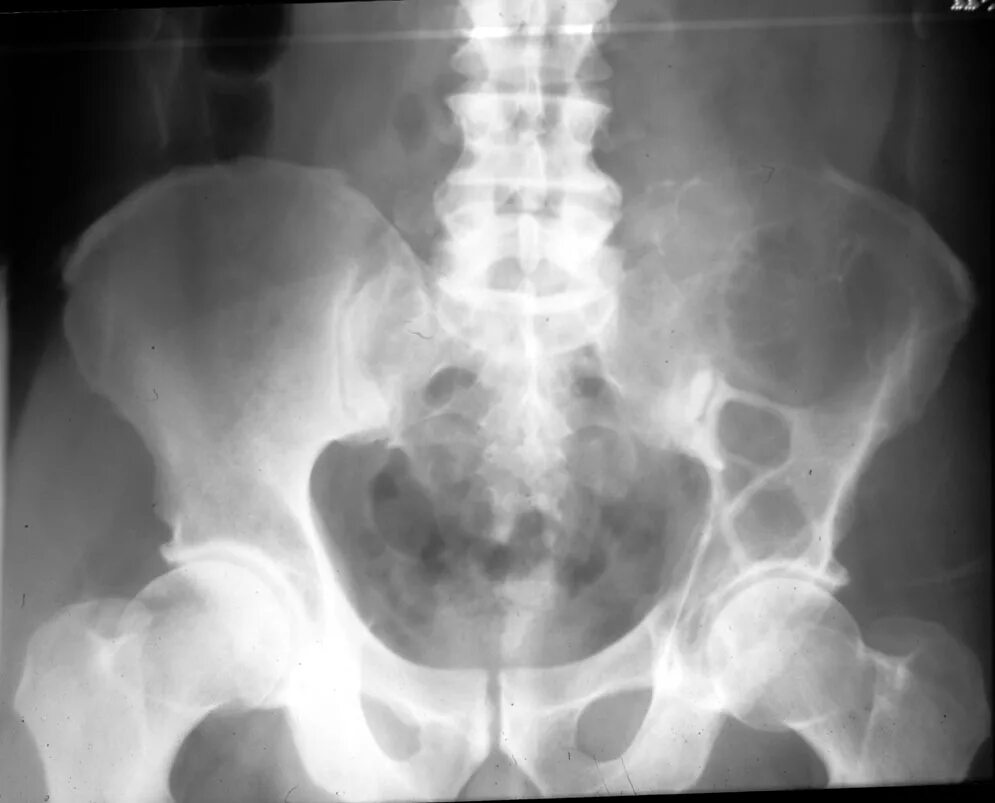

Метастазы в тазу